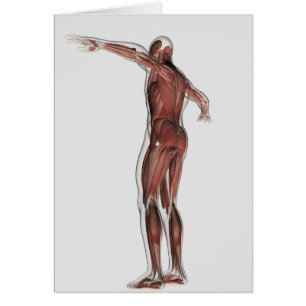

Anatomie Du Système Musculaire Masculin, Vue Posté

Prix de vente 6,48 $CA. Prix Initial 7,20 $CA.